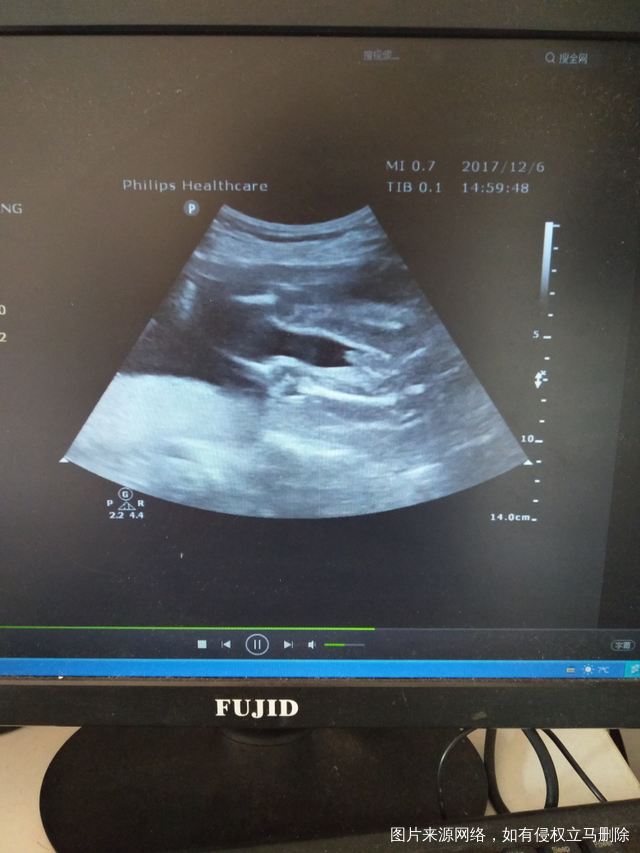

可以帮我看下是男孩还是女孩吗?